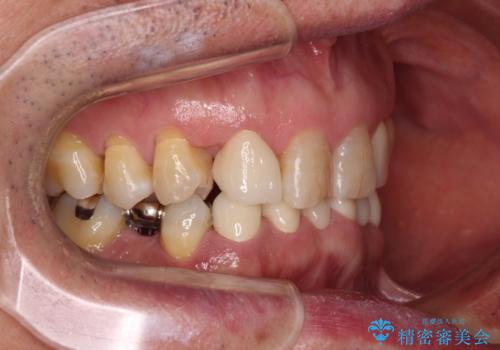

- 乳歯や矮小歯が多くある前歯部の審美障害が気にして来院された患者様です。

上顎の矮小歯は隙間が多く、歯軸の傾斜も大きかったため、部分矯正により補綴治療前に歯の位置を整えることとしました。

下顎の乳歯は支台歯として機能することは困難と思われたので、事前に抜歯をし、上顎の矯正治療終了のタイミングに合わせて、セラミックブリッジにて補綴治療することとしました。

前歯部はディープバイトという、上顎前歯が下顎前歯に深く覆い被さる咬合であったので、理想的には全顎矯正が必要となりますが、今回は患者希望により前歯部のみの部分矯正で対応しました。そのため下顎犬歯の神経を取り除くことになってしまったのは心残りであります。